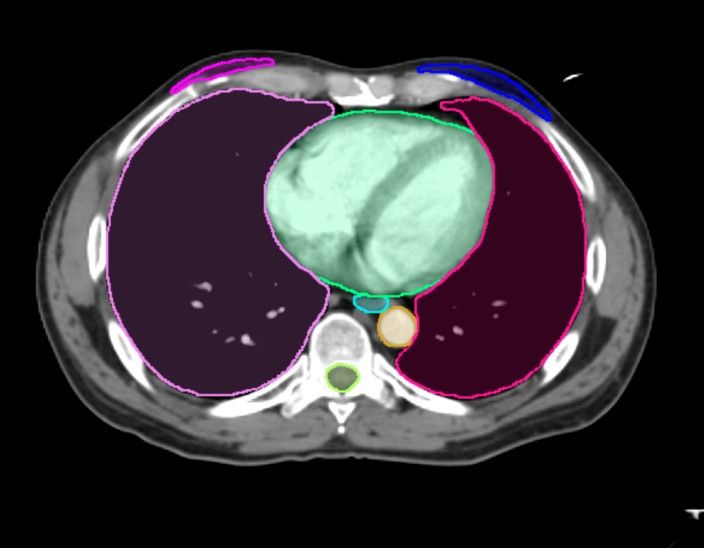

A hybrid computed tomography radiomics model demonstrated up to an 86 percent area under the curve in predicting microvascular invasion in patients with hepatocellular carcinoma in a recently published study.